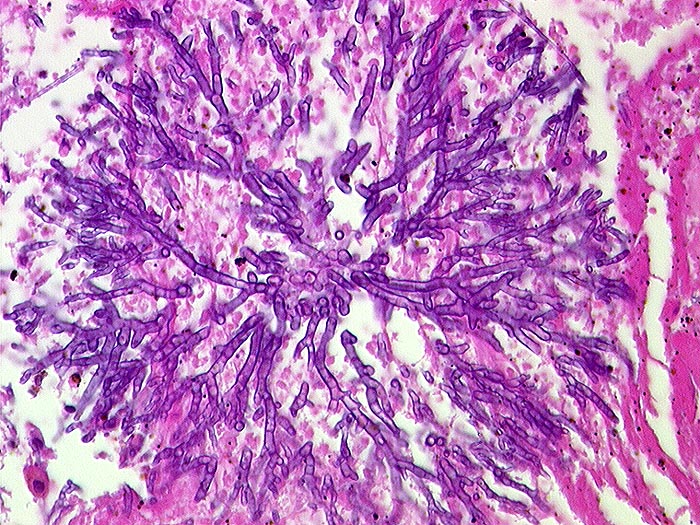

Aspergillen gehören in die Gruppe der Schimmelpilze und wachsen ubiquitär auf organischen Stoffen. Der Erreger ist charakterisiert durch echte septierte Hyphen von 3 bis 6 Mikrometer Durchmesser. Die Hyphen verzweigen sich in einem Winkel von 45 Grad. Selten sind auch die (> 10851) (> 10849) Fruchtköpfe (Conidiophoren) nachweisbar. Aspergillusinfekte manifestieren sich je nach Resistenzlage als Aspergillom, invasive Aspergillose oder allergische Aspergillose. Der Nachweis von Aspergillus beweist noch nicht eine klinisch relevante Infektion.